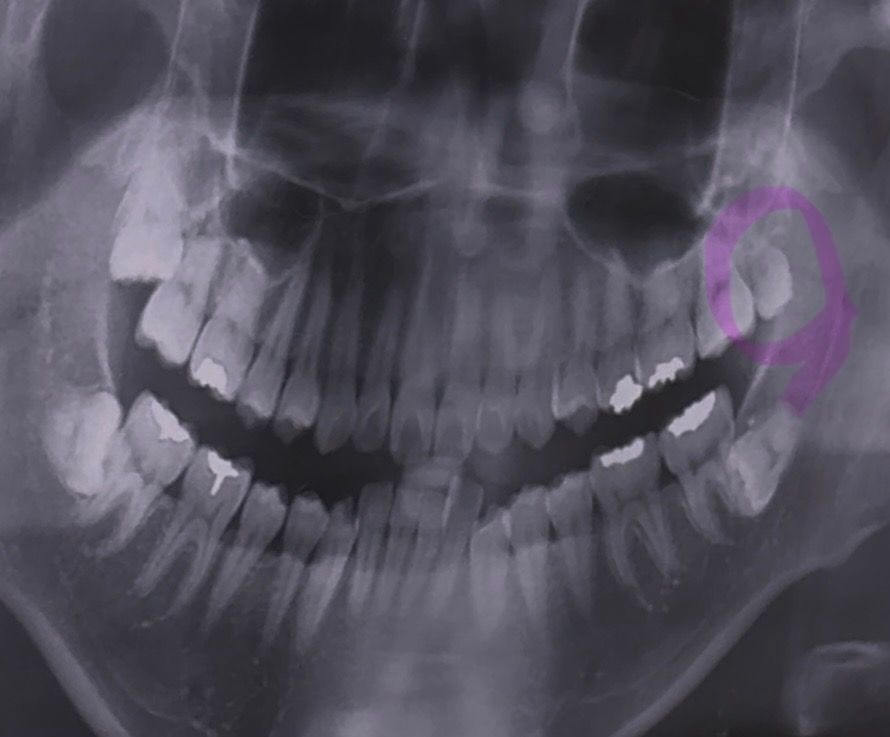

병원에서 윗쪽에 표시한 사랑니에 충치가 있다고 하는데 그냥 뽑는게 맞나요?

반듯하게 난건 나중에 스페어로 쓸수있다 그래서 고민이에요...

• 1번 째 사진